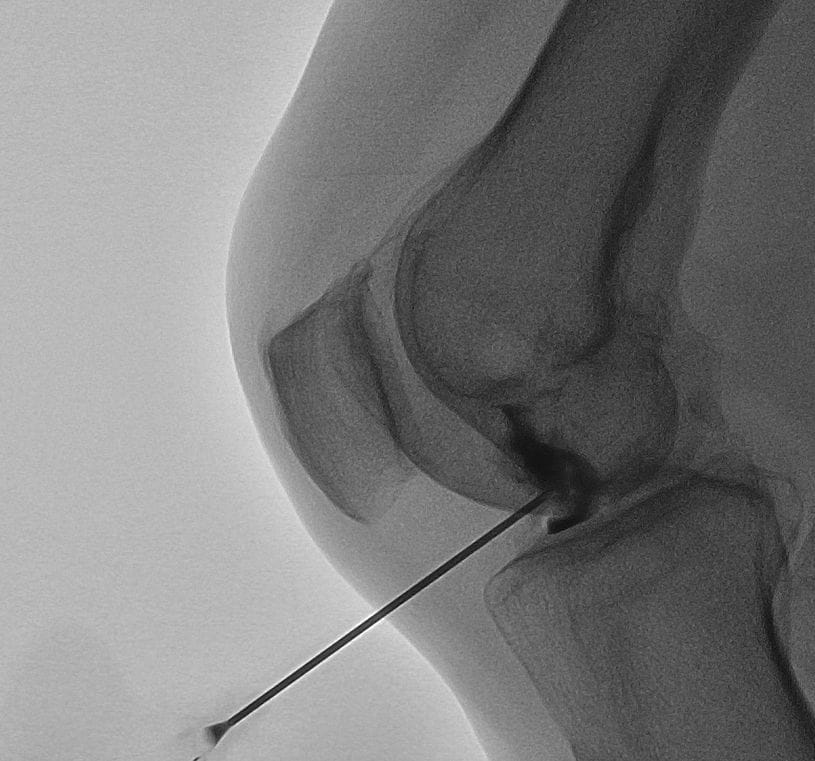

Ulterior, plasma bogată în trombocite obținută este folosită pentru a fi injectată în articulația genunchiului. În acest proces, medicul utilizează tehnologia ultrasonografică pentru a se asigura că injecția este efectuată în locul corect. După tratament, pacientul se odihnește pentru o perioadă, după care poate să se întoarcă acasă. Deoarece pot apărea durere și rigiditate în zona injectată, pacientul ar trebui să fie însoțit acasă de o persoană de încredere pentru a asigura un transport sigur. Tratamentul PRP este considerat o metodă eficientă în reducerea durerii de genunchi și în îmbunătățirea sănătății articulației.